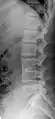

Block vertebrae of the cervical spine (vertebrae 4 and 5). Probably based on degenerative or inflammatory changes.